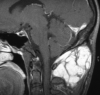

Histologic patterns of cellular architecture often suggest a tissue diagnosis. Distinctive histologic patterns seen within the peripheral nerve sheath tumor schwannoma include the Antoni A and Antoni B regions. The purpose of this report is to review the significance of Antoni regions in the context of schwannomas.